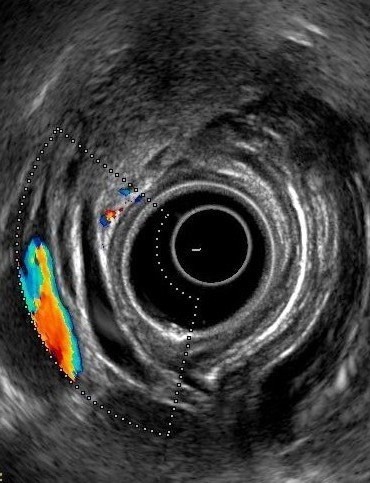

On radial endosonography, absence of the “stack

sign” has been suggested as a useful criterion for diagnosing pancreas divisum

(Figure 1) [6]. To obtain the stack sign, the echo endoscope is positioned in

the duodenal bulb in the long position and the balloon is inflated after

positioning the tip of the endoscope in the apex of the bulb. From this

position, the distal common bile duct, ventral pancreatic duct and the portal

vein can be seen to run in parallel being stacked together. The bile duct will

be closest to the transducer.

Figure 1. Radial EUS: stack

sign showing common bile duct, pancreatic duct and portal vein. |